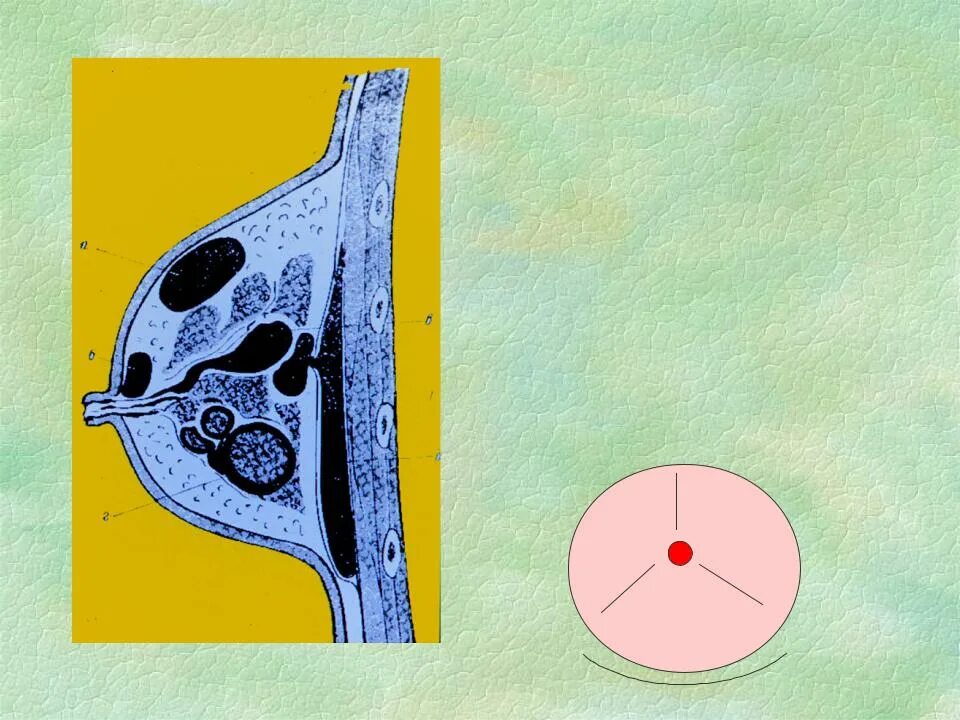

Мастит по студенцову